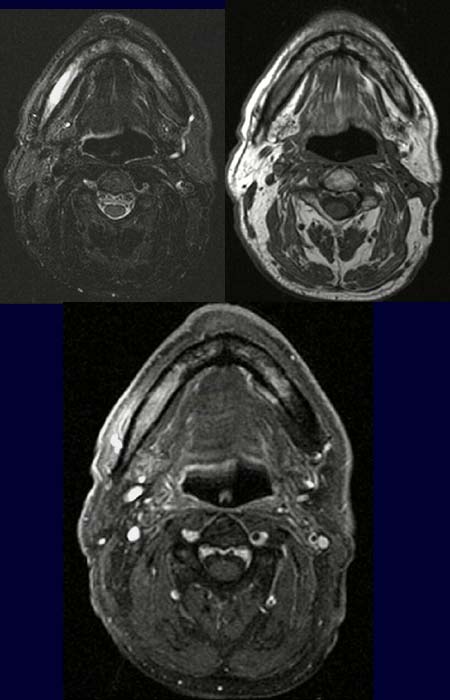

Patient mit Z.n. enoraler Tumorresektion eines Mundbodenkarzinoms rechts und anschließend interstitieller Radio-Therapie.

Klinisch kleines Ulcus im Bereich der ehemaligen Tumorregion. Bioptisch lässt sich hier nur entzündliches Gewebe diagnostizieren. Anhaltende Schmerzen im Bereich der linken Wange- und Kieferregion.

In der T2-Wichtung (linkes Bild oben) kommt der rechte Alveolarknochen des Unterkiefers deutlich signalangehoben zur Darstellung.

In der T1-Wichtung nativ ohne Fettsättigung (rechtes Bild oben) ist dieser Bereich signalarm.

In der T1-Wichtung nach Kontrastmittelgabe mit Fettsättigung (Bild unten)kommt dieses Areal wieder deutlich signalreich zur Darstellung.

Osteomyelitis

Osteoradionekrose